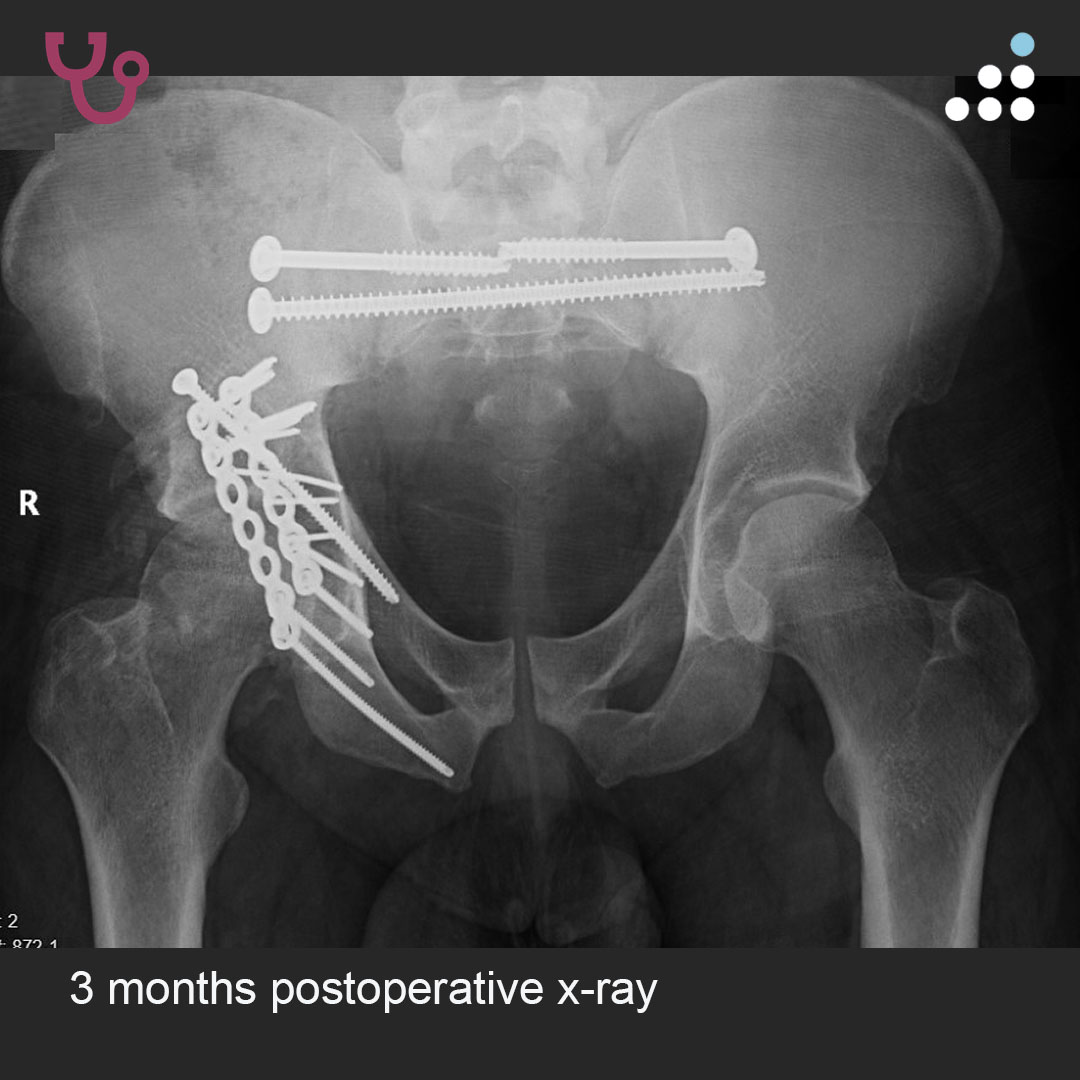

Can you answer our free question of the day? A patient presents to the trauma bay after involvement in a motor vehicle collision. Radiographs obtained in the trauma bay demonstrate a right distal femur fracture, as seen in Figure A. In surgery, the articular block is reduced, and reduction is held with headless compression screws. A retrograde intramedullary nail is then placed. After nail advancement, a varus and recurvatum deformity is noted at the fracture site with intraoperative fluoroscopy, as demonstrated via illustrations in Figures B and C. Placement of blocking screws in which locations (A - H) from Figure B and C would help correct this deformity? 1. B + E 2. A + G 3. B + F 4. C + H 5. D + H QID: 217509 Comment your answer below, then check to see if you got it correct by clicking the link below to see the answer & explanation. bit.ly/3OxP8sP #orthopedics #orthopedicsurgeon #orthopaedics #orthopaedic #orthopedic #ortholife #orthobullets #orthoresidents #orthoresident #orthoresidency #medicalschool #medicalstudent #medstudent #doctor